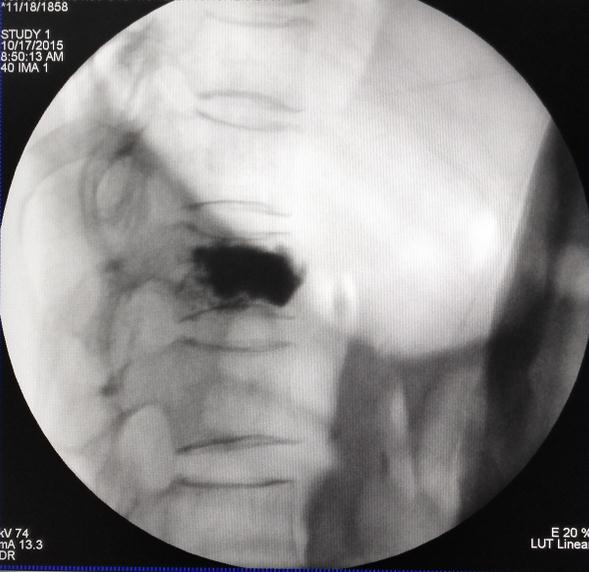

2.椎间孔镜技术:目前国际脊柱微创外科领域公认的成熟技术。我院引进国际先进的新一代Maxmore椎间孔镜,具有更安全、更精准、更有效的治疗腰椎间盘突出症。具有微创:不开刀,切口仅7mm,只缝一针;安全性高:局部麻醉,可视化,出血少,术中能与病人沟通;并发症少:创伤小,很少形成血肿,感染可能性小,不损伤脊柱的稳定性;康复快:术后次日可下床活动,循序渐进开始康复功能锻炼;满意度高:立即缓解疼痛;费用低:较开刀费用节省约50%。